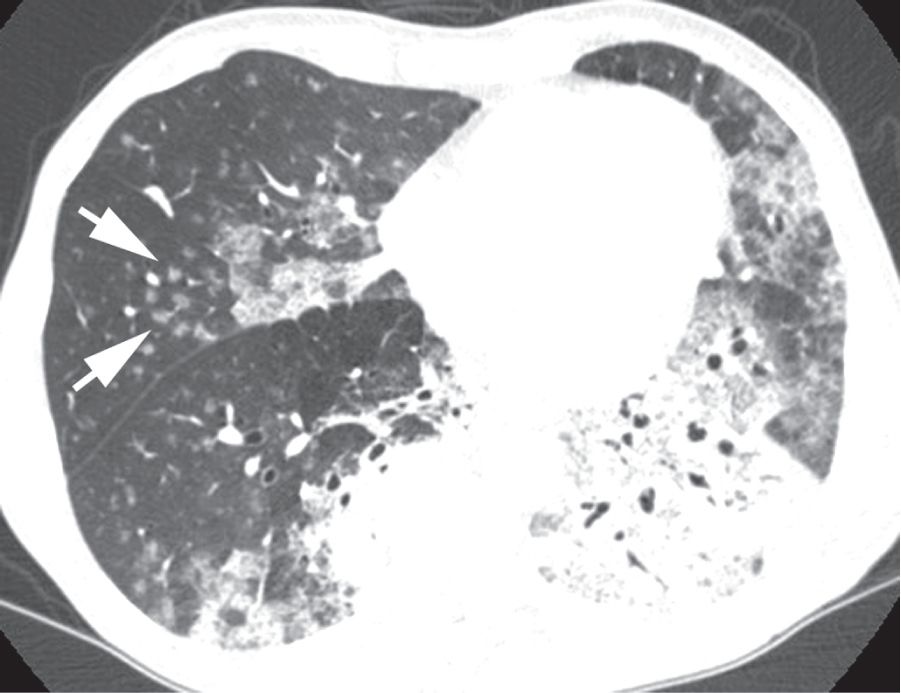

图2-5 实变:腺泡或气腔结节

胸部平片显示斑片状左上叶大叶性肺炎,致密实变影边缘可见直径小于1cm 的边界不清的结节样密度增高影( 箭头),代表气腔或腺泡结节;B. 双肺实变患者CT 显示( 层厚5mm),左肺下叶可见空气支气管征,并显示斑片状实变和毛玻璃样致密影, 右肺中叶、下叶可见气腔结节( 箭头)。这些结节边界不清,直径5 ~ 10mm,呈小叶中央分布